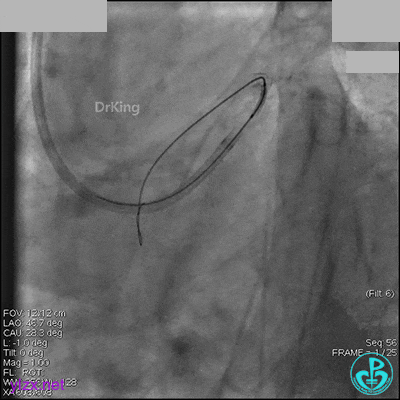

AL 1.0指引导管到位,简单短时尝试导丝不能顺利通过前降支或回旋支病变。改变策略处理右冠脉病变,计划植入2枚支架。AL指引导管到位,Sion blue导丝到达右冠脉远端。导丝通过后1.5mm及2.5mm球囊14~16atm充分扩张中段病变。

右冠脉中段充分扩张后欲植入3.5×38mm支架时,支架难以通过中远段扭曲处,且指引导管、导丝弹出飞扬。反复尝试导丝重新到达右冠脉远端时通过不顺利,局部造影剂滞留,远端血流接近3级。

1周后再次上台,右冠脉3级血流,3段局限性严重狭窄,内膜模糊,应该是上次操作夹层遗留下的血肿。

先处理前降支开口严重狭窄并顺利植入前降支到左主干支架。